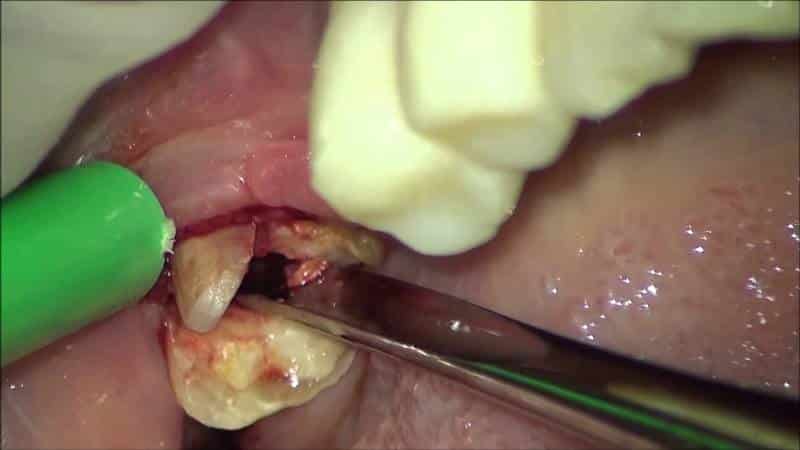

В таких случаях необходимо незамедлительно обратиться к врачу, сделать рентгеновский снимок и провести лечение или удаление зуба мудрости, чтобы предотвратить осложнения. Стоматологи при лечении таких патологий вскрывают слизистую оболочку, промывают полость и назначают противовоспалительные препараты. В некоторых случаях, при повторном воспалении, может потребоваться удаление зуба до его полного прорезывания. Еще одной распространенной проблемой во время роста зуба мудрости является появление кариеса.

Удаление зуба мудрости может иметь последствия, такие как травмирование челюсти с медленным заживлением раны и осложнениями. После удаления может возникнуть ноющая боль, свидетельствующая о воспалении лунки. Нормальное заживление происходит прикрытием лунки кровяным сгустком, который защищает ее от микробов. Полоскание после удаления не рекомендуется, так как это может привести к инфекции. В некоторых случаях может потребоваться повторное хирургическое вмешательство, особенно если появляется онемение языка, губ и подбородка, которое длительное время не проходит.